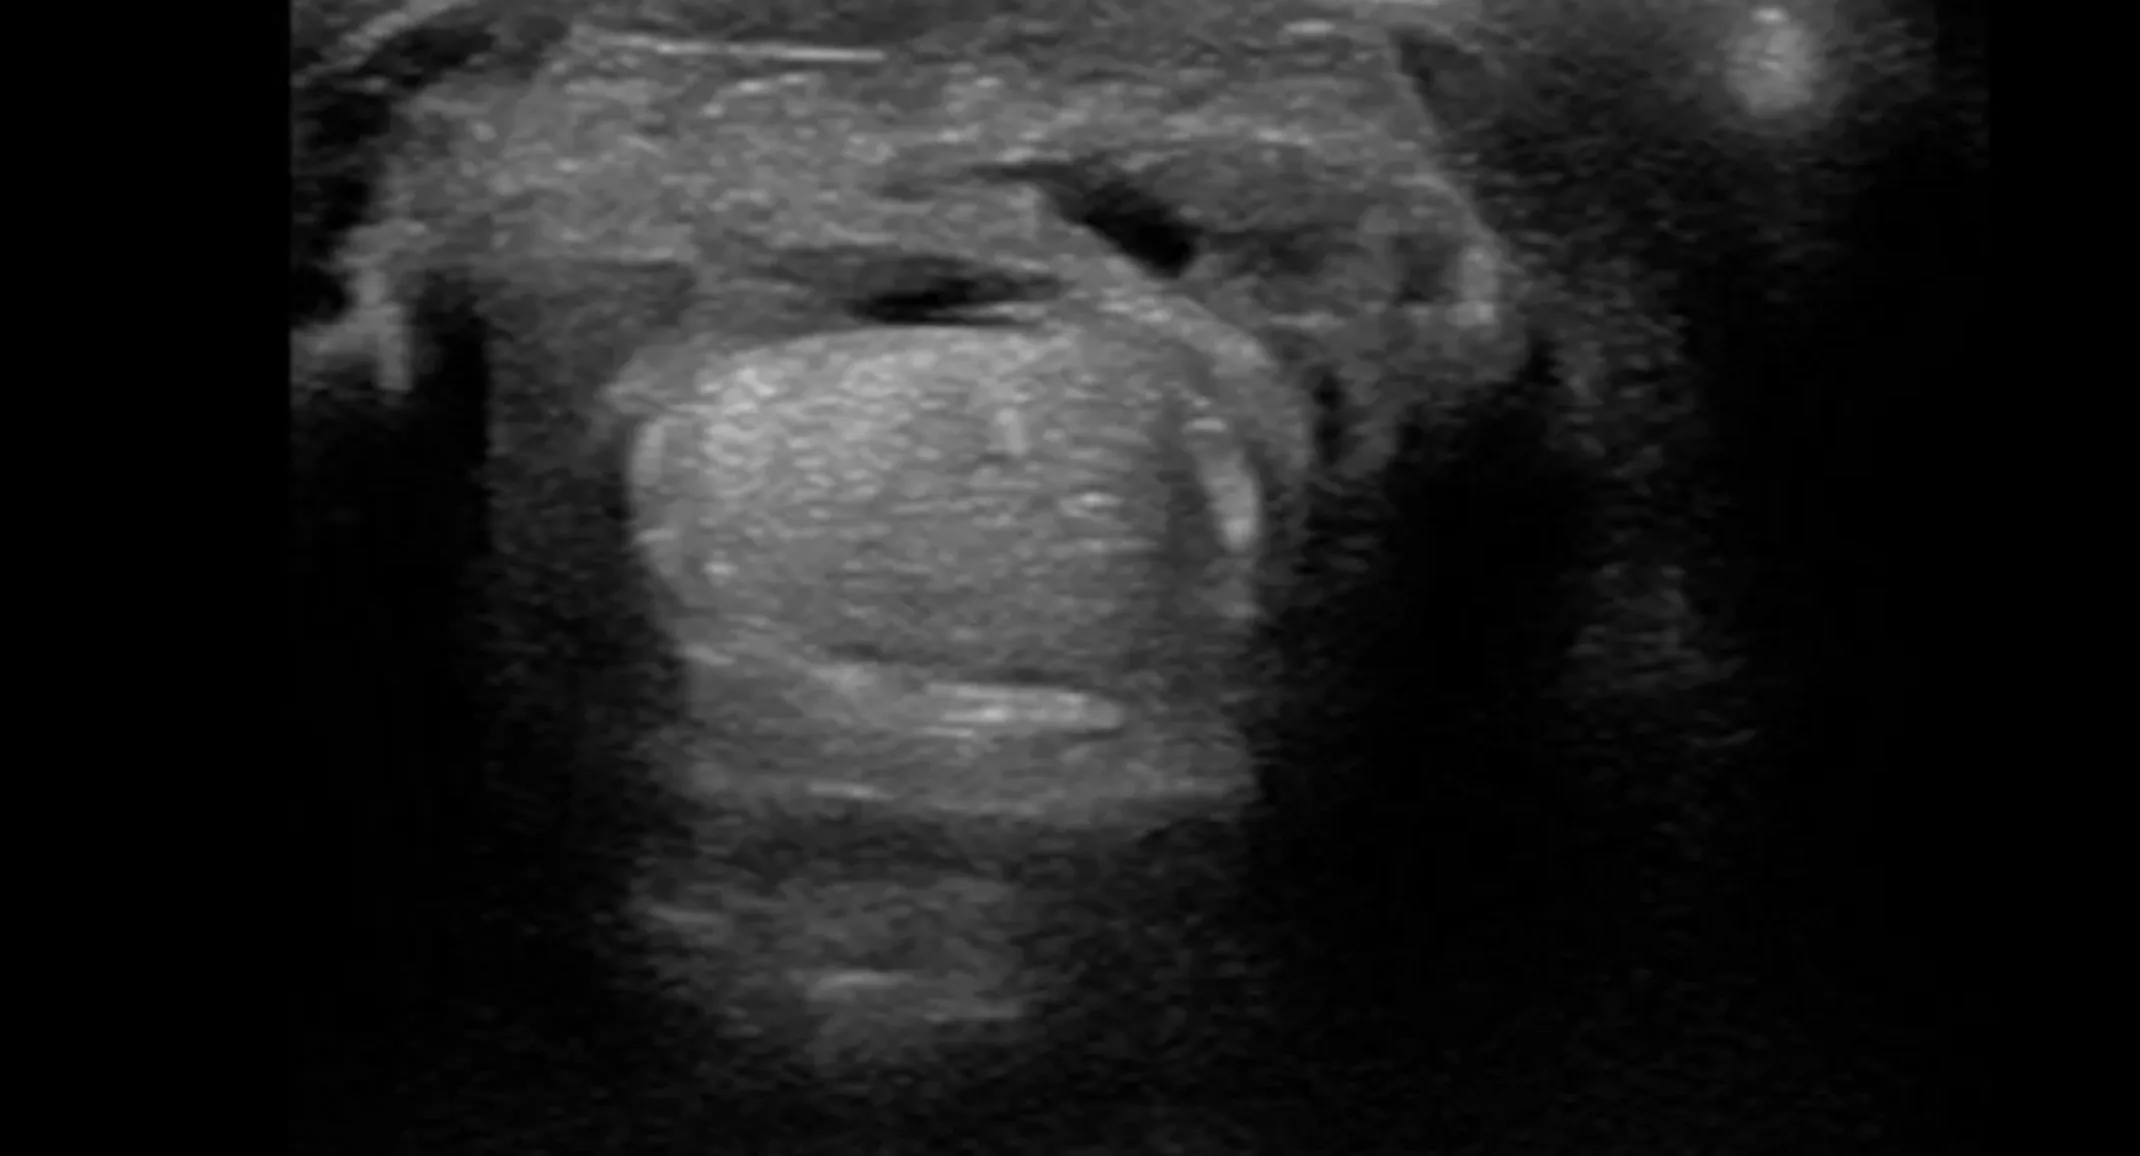

Ultrasound examination confirmed tendonitis of the SDF. Small multifocal tears and diffuse hypoechogenicity was visualized in approximately 2/3 of the tendon’s length in the metacarpal region.